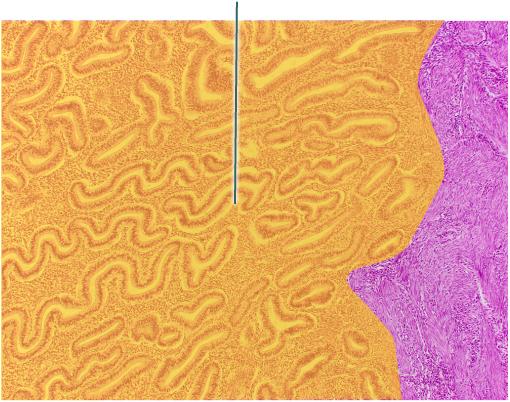

Identify the highlighted layer of the uterine wall

Endometrium

Identify the highlighted uterine layer.

Myometrium

Which hormone stimulates contraction of the highlighted layer? (Myometrium)

Oxytocin